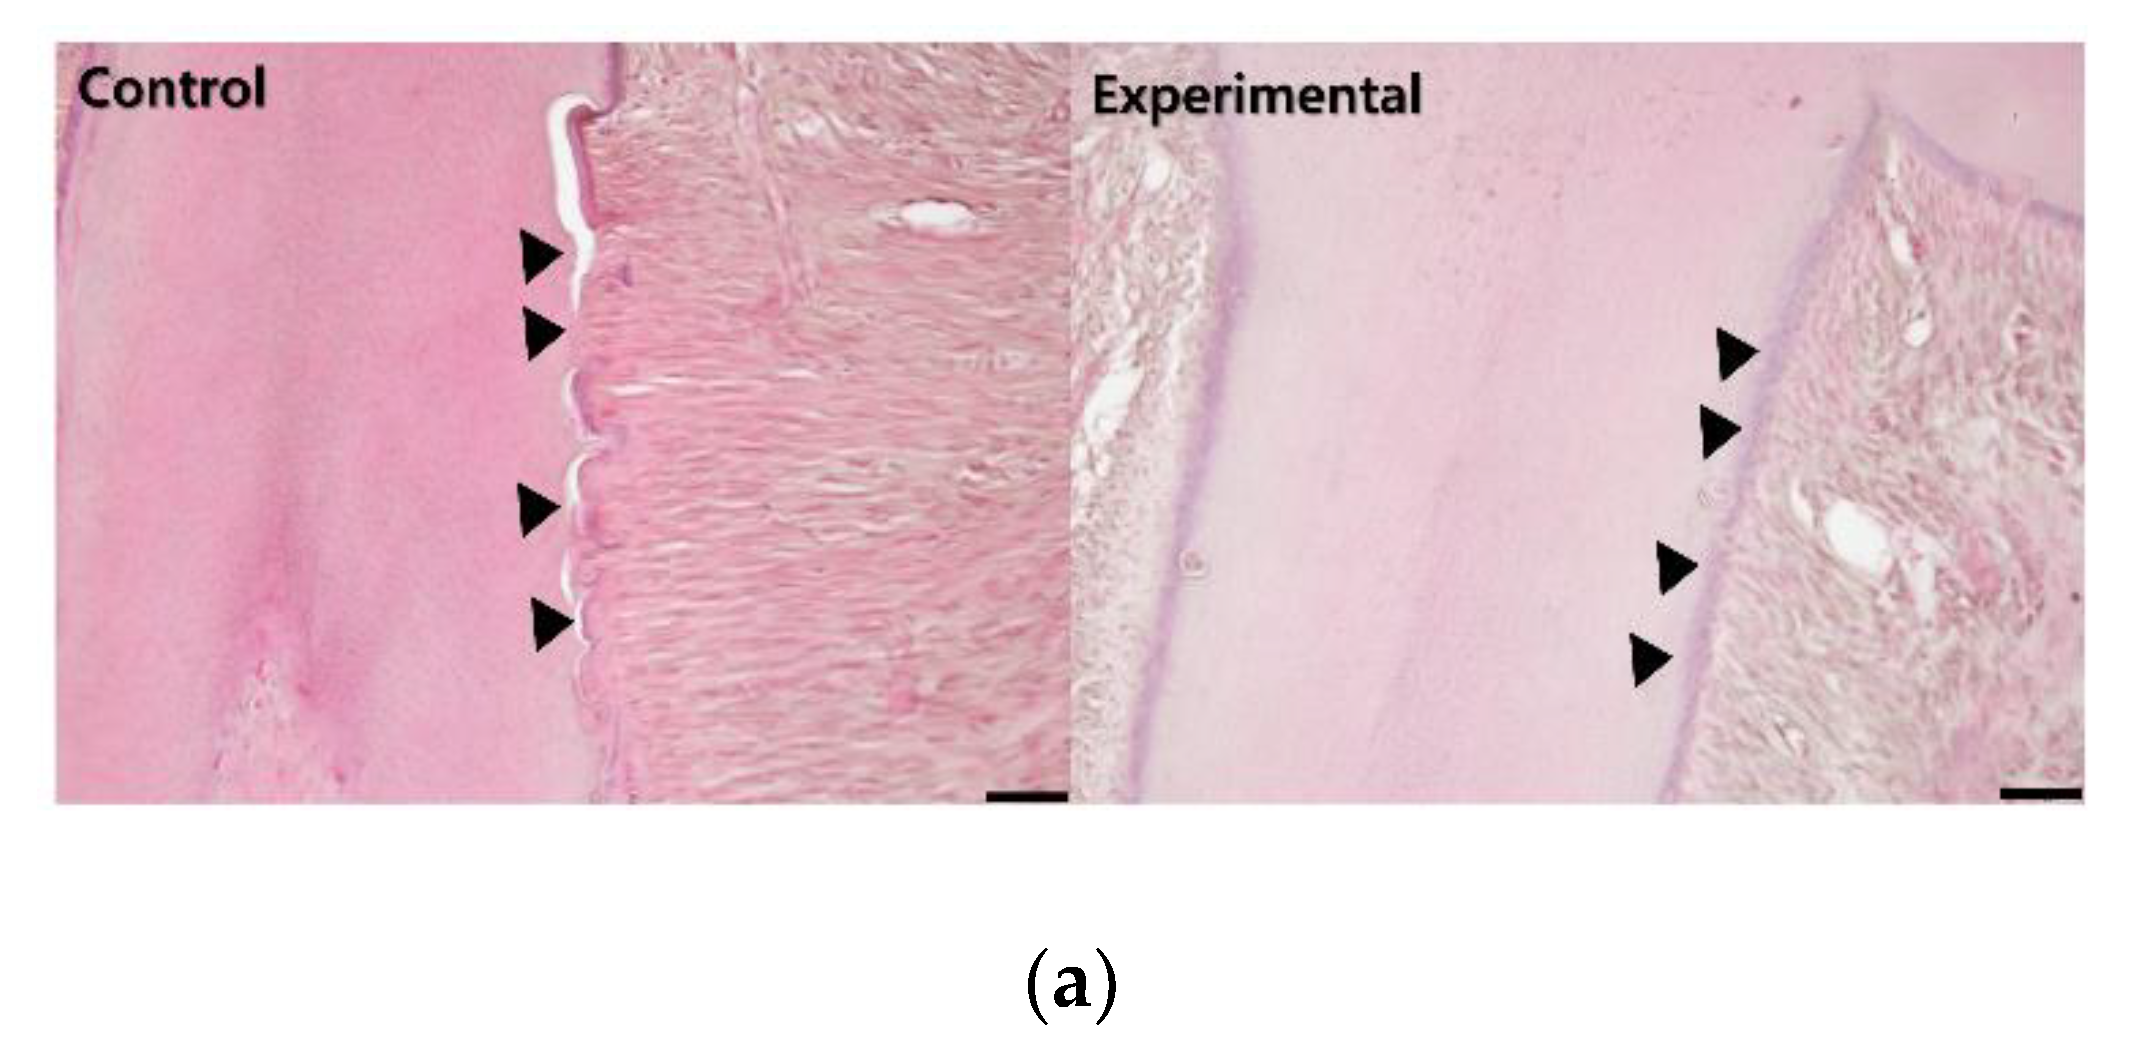

3.1. The Application of 4HR Inhibited Root Resorption during OTM

3.2. 4HR Increased OPG, RANKL, AP, and Runx2 Expression in Tissue